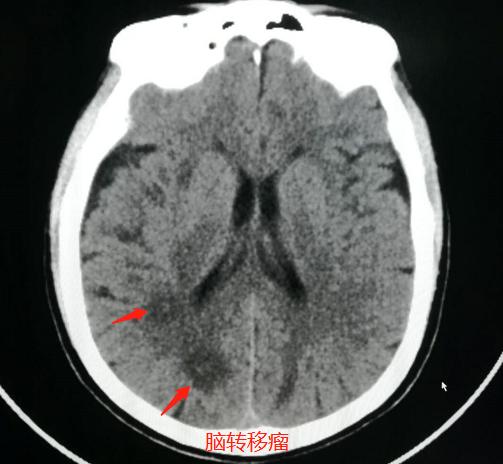

病例2,女性患者,67岁,头晕一周行脑CT检查:

发现脑内多发类圆形低密度影,内部似乎还有稍高密度小结节,可疑脑转移瘤,于是进一步肺CT检查:

果然发现了右侧肺癌脑转移,伴有胸膜牵拉和增厚。

病例3. 女性患者,83岁,突发头晕、言语不清1天,怀疑脑血管意外做颅脑CT:

发现脑内多发的小结节,比周围脑组织密度略高,但周围没有低密度水肿带。

询问病史,老人没有去过疫区,也没有吃过生猪肉等,不支持寄生虫病,那就要想到不典型脑转移瘤的可能,于是住院进一步检查肺部:

发现了右下肺癌,伴有肺底部膈胸膜牵拉,符合肺癌并脑多发转移瘤。